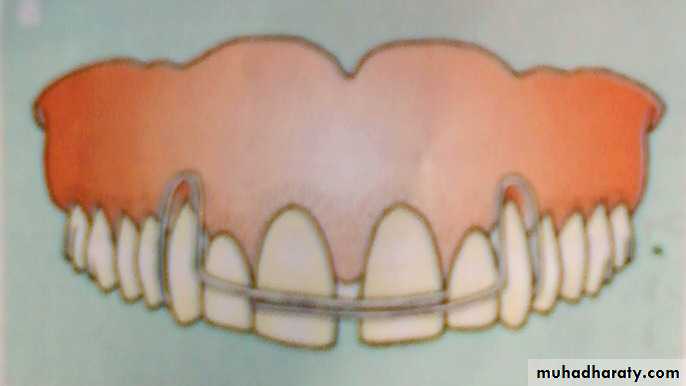

A, Closure of a midline diastema can be accomplished with a removable appliance and finger springs to tip the teeth mesially.

Closure of a diastema with a fixed appliance, immediately after space closure, the teeth are retained, preferably with, (D) a fixed lingual retainer at least until the permanent canines erupt.